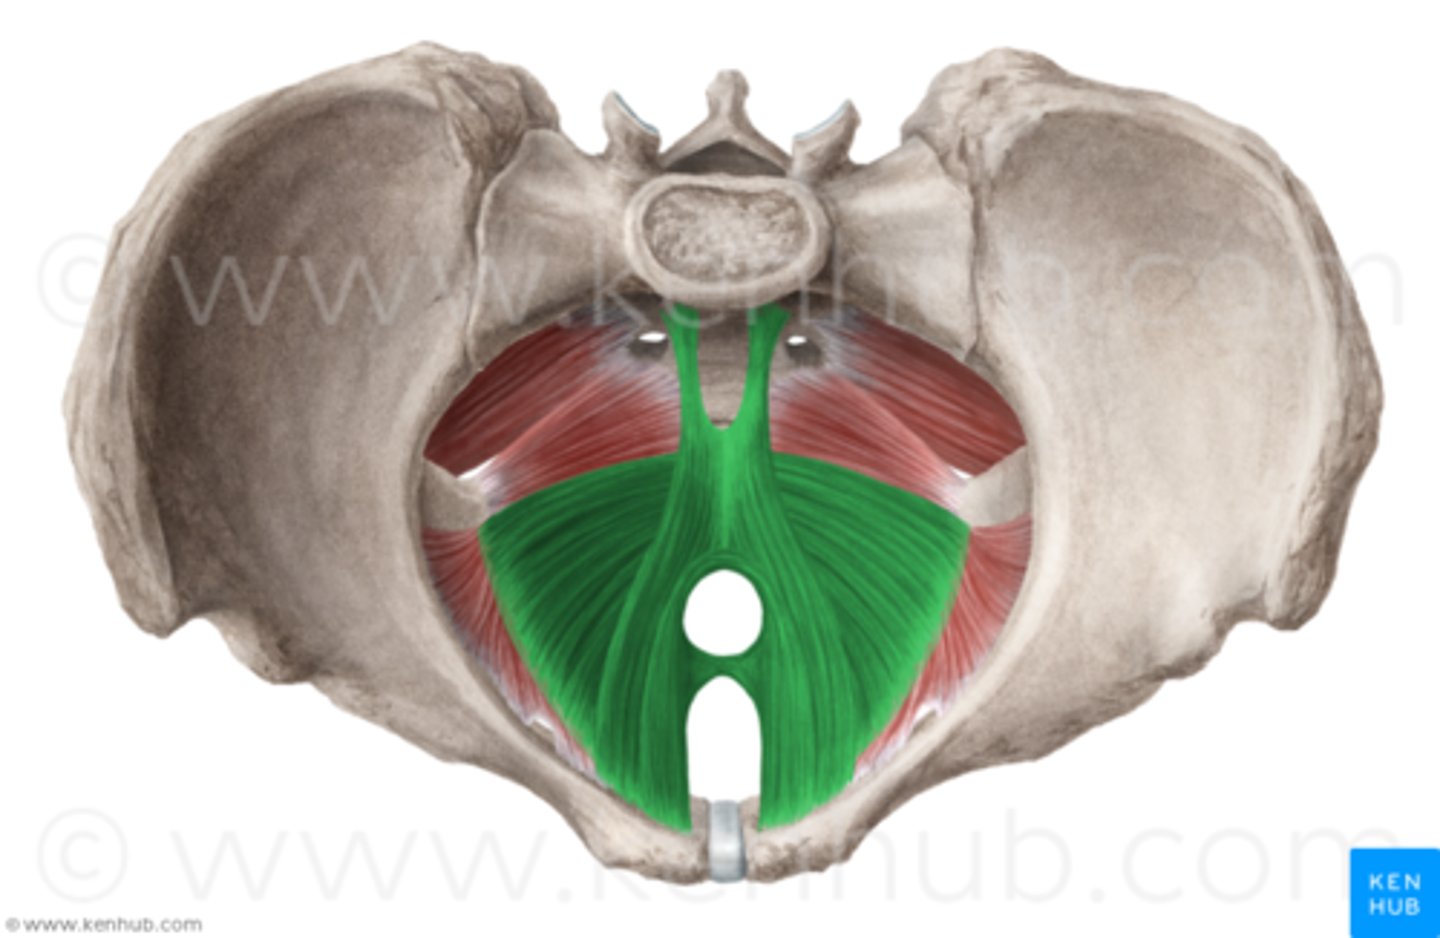

levator ani muscles

puborectalis, pubococcygeus, iliococcygeus

pelvic diaphragm (proper)

levator ani and coccygeus

Pubococcygeus

O: pubic bone (lateral to puborectalis)

I: coccyx

A: controls urine flow, contracts during orgasm